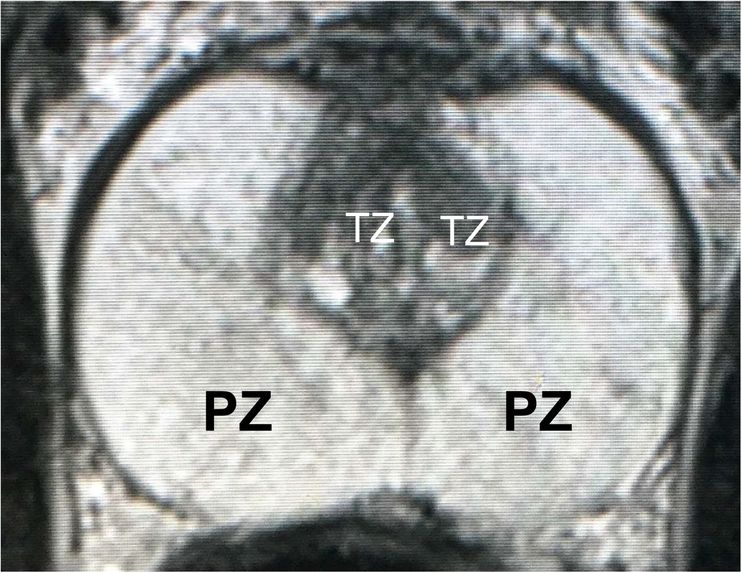

Figure 3: MRI slices (first and thrid rows) from one study with labels (second and fourth rows).

The prostate data set was acquired at Radboud University Medical Center, Nijmegen Medical Centre, Nijmegen, The Netherlands. It consists of 48 prostate multiparametric MRI (mpMRI) studies, 32 of them have corresponding region-of-interest (ROI) targets (background= 0, TZ= 1 and PZ= 2). Each study contains approximately 15 to 20 slices of MRI images, resulting in 602 images in total. Figure 3 shows the 20 slices from one study. The first and last few MRI slices contain little segmentation information. Therefore, to simplify the problem, we will discard the first and last 5 MRI slices from each study. We will use 10 studies (95 images) as the test set and the remaining 22 studies (187 images) as the training set.